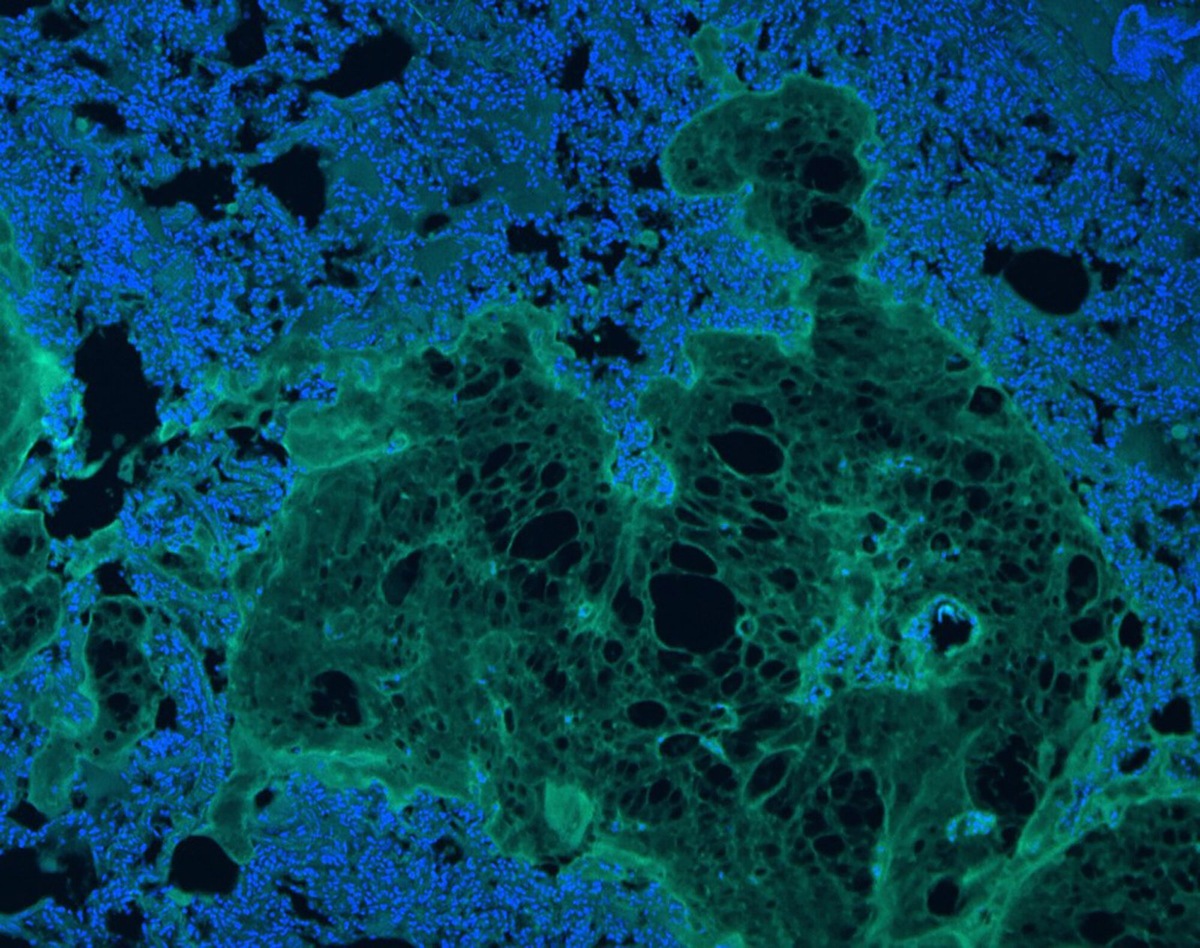

Иммунофлуоресцентное окрашивание макрофагов (зеленый) и ядер (синий) на границе гидрогеля и ткани через семь дней после надрезов артерий у крыс.

Иммунофлуоресцентное окрашивание макрофагов (зеленый) и ядер (синий) на границе гидрогеля и ткани через семь дней после запечатывания разрезов легких у крыс.